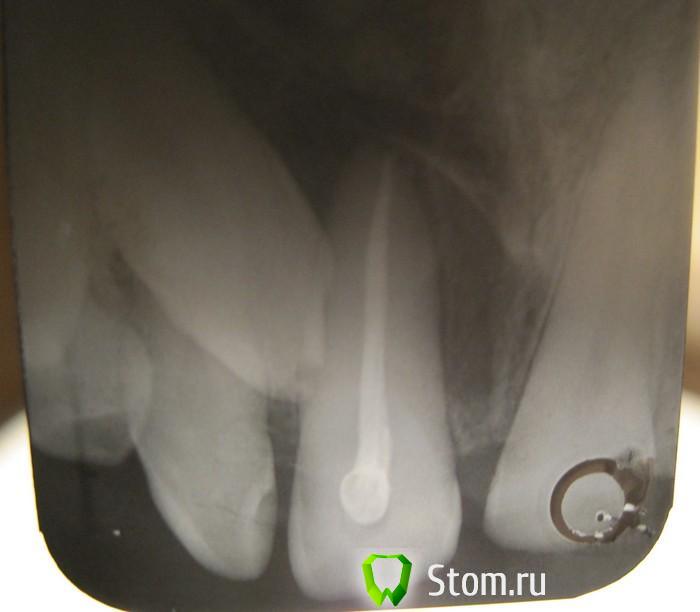

Мармышка Опубликовано 21 января, 2012 Автор Поделиться Опубликовано 21 января, 2012 вот ещё попыталась в домашних условиях сфотографировать дентальные снимки. Первый снимок до лечения и дот панорамника, второй- после. Извиняюсь за качаство) Ссылка на комментарий

Мармышка Опубликовано 21 января, 2012 Поделиться Опубликовано 21 января, 2012 В общем, вот такая ситуация. Человек жил с этим 33 года и не подозревал о такой лежачей красоте) 30 декабря начал болеть 21 зуб, при т ом жалобы, как при периодонтите, очень болел при дотрагивании и даже уже начала отекать переходная складка. Зуб интактный, сделали снимок, на 100 процентов была уверена, что периодинти и всё дело в нём. Думала, открыть помыть, кальций временно, снять острые явления, довести лечение 21 до конца, а уж потом разбираться с ретенированной тройкой. Но оказалось, что 21 живой зуб!!! в общем, пришлось временно запломбировать, чтобы сделать панорамник (к сожалению, у нас делают панорамники в другой клинике и по предварительной записи). В общем, после консультации с хирургом пришли к выводу, что тройка начала упираться в 21, и надо её убирать. 21 залечила под анестезией. Потом выложу фото. Но там такая деструкция кости...((((Самое печальное, что ситуация эта у очень близкого мне человека... закон подлости..были ли у вас такие ситуации? очень страшно, что 21 зуб полетит во время операции. Во вторник поедем на 3В диагностику, хочется посмотреть с какой стороны тройка сидит и на каком расстоянии к соседним зубам. Ссылка на комментарий

kriokov Опубликовано 21 января, 2012 Поделиться Опубликовано 21 января, 2012 почему именно вестибулярно? у меня тоже такая мысль была, но он говорит, что нёбо болит...когда дело касается наших близких, все мысли куда-то улетучиваются(((сложно сказать как он лежит, оба снимка практически в одной проекции. Чтобы по правилу щечного обекта определиться надо второй снимок делать в эксцентричной проекции. Ссылка на комментарий

kriokov Опубликовано 21 января, 2012 Поделиться Опубликовано 21 января, 2012 +1 за вестибулопозицию клыка. Прежде чем удалять посоветуйтесь с ортодонтом. думаю вытянуть будет вернеза небное положение, по анализу ОПТГ. Размеры коронки ретенированного клыка увеличены в размере и растянуты, а корень нет, значит обьект (коронка) близко к фокусу- т.е небно Ссылка на комментарий